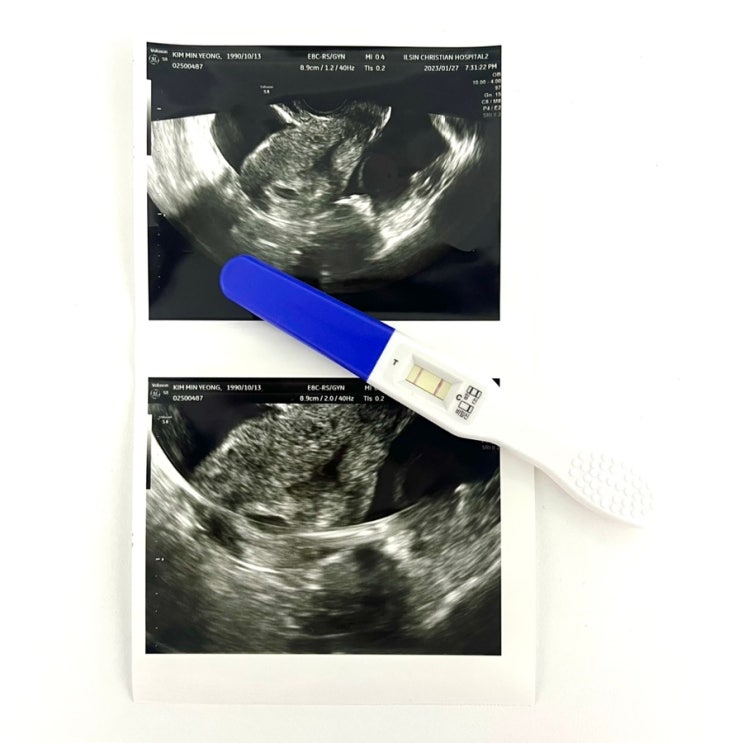

[임신 5주차/6주차] 일주일만에 드라마틱한 초음파 변화(난황, 심장소리)& 보건소 물건수령 후기

전 테스트기로 임신확인 후 3일 후에 병원 갔었어요 그때가 5주차였었는데 첫 초음파때 난황도 안보이고 아...